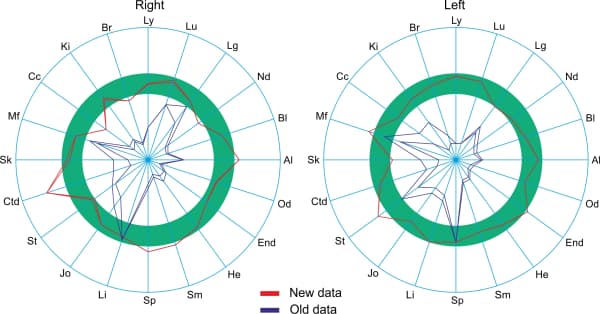

The following depicts the total deviation from the norm from the right (Fig. 1) and from the left (Fig. 2), under the influence of an Aires Defender.

The subject has a pronounced asymmetry in the initial measurements: 33 from the right and 44 from the left, which indicates a desynchronization of the right and left cerebral hemispheres.

After 46 hours of using the Aires Defender, the value dropped on both sides to 22 and the asymmetry was gone. After 98 hours of using the Aires Defender, the value dropped to a minimum of 5 on both sides.

An electroencephalogram is a plot of a recording of the bioelectric activity of the cerebrum in the frequency range from 0.3 to 50 oscillations per second, divided into a number of bands (delta, theta, alpha, beta, gamma). An EEG can be used to evaluate processes occurring in the cerebrum and can be successfully employed in the diagnosis of various diseases and conditions of the central nervous system. The cerebral hemispheres generate radiation independently and may operate in concert or in an uncoordinated way. The cerebral hemispheres differ in their functions. The right hemisphere perceives intuitive, figurative, and abstract information, while the left hemisphere perceives concrete, logical information. For example, the center of speech is located in the left hemisphere. Human evolution is a result of both growth in the capacity of each hemisphere and an increase in the number and quality of interconnections between them. The number of inter-hemisphere connections is a manifestation of the coordination of the two hemispheres. A person is competent in all areas (physical, mental, social) only when the maximum number of interconnections between the hemispheres have developed in the brain and the interactions between them are harmonious and coordinated. The degree of coordination between the interconnections is marked by color in the charts: maximum coordination – pink, average – red, imbalance – dark blue, maximum imbalance – light blue.

We present examples of changes observed in EEG parameters during use of the Aires Defender. We note that in no case was there an worsening of the initial measurements. For convenience, the EEG being compared are placed next to each other. On the left is the initial data. One the right is the baseline of Aires Defender usage.

It can be seen in Figure 2 that the initial EEG recorded destructive interaction (dark blue) in the delta-1 band and the depletion of intercenter links. After a month of using the Aires Defender, the destructive interactions were eliminated, and the intercenter links in the delta-1 band were restored and concentrated. Ideally, each center should have a coordinated, consonant link (pink or red) with all others, which would increase its functional capabilities and the abilities of the entire system as a whole.

based on cross-correlation in the delta-1 band.

based on cross-correlation in the delta-2 band.

It can be seen in Figure 3 that the initial EEG recorded destructive interaction (dark blue) and the depletion of intercenter links, also in the delta-2 band. After a month of using the Aires Defender, the destructive interactions were eliminated, and the intercenter links in the delta-2 band were restored and concentrated.

Fig. 4 – The depletion of intercenter links was observed in the initial EEG. After a month of using the Aires Defender, the intercenter links in the theta band were restored and concentrated.

based on cross-correlation in the theta band.

based on cross-correlation in the alpha band.

Fig. 5 also shows a depletion of intercenter links in the initial EEG. After a month of using the Aires Defender, the intercenter links in the alpha band were restored and concentrated.

Fig. 6 – Destructive interactions (dark blue) and the depletion of intercenter links were observed in the initial EEG. After a month of using the Aires Defender, the destructive interactions were eliminated, and the intercenter links in all frequency bands were restored and concentrated.

based on cross-correlation in all bands.

Figure 7 shows the phase delays (blue and dark blue) at the different leads before the application of the Aires Defender. This creates a functional asymmetry of the hemispheres. After application of the Aires Defender, symmetry is restored.